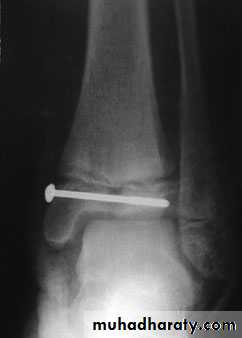

3. Interna1 fixation:

Fractures that cannot be reduced only by operation.

Failure of conservative treatment.

Unstable fr that frequently redisplaces after closed reduction e.g. fr of forearm or mid shaft of femur.

Fr that poorly heals and takes long time to do so in conservative way e.g. femoral neck fr.

Pathological fractures.

Polytraumatized patient with multiple fr.

Patients that have nursing difficulties as in elderly, paraplegics, chronically diseased...etc

Fr with vascular injury that needs surgical intervention.

The indications of open reduction and internal fixation (ORIF)

PLATE & SECROW FIXATIONDHS